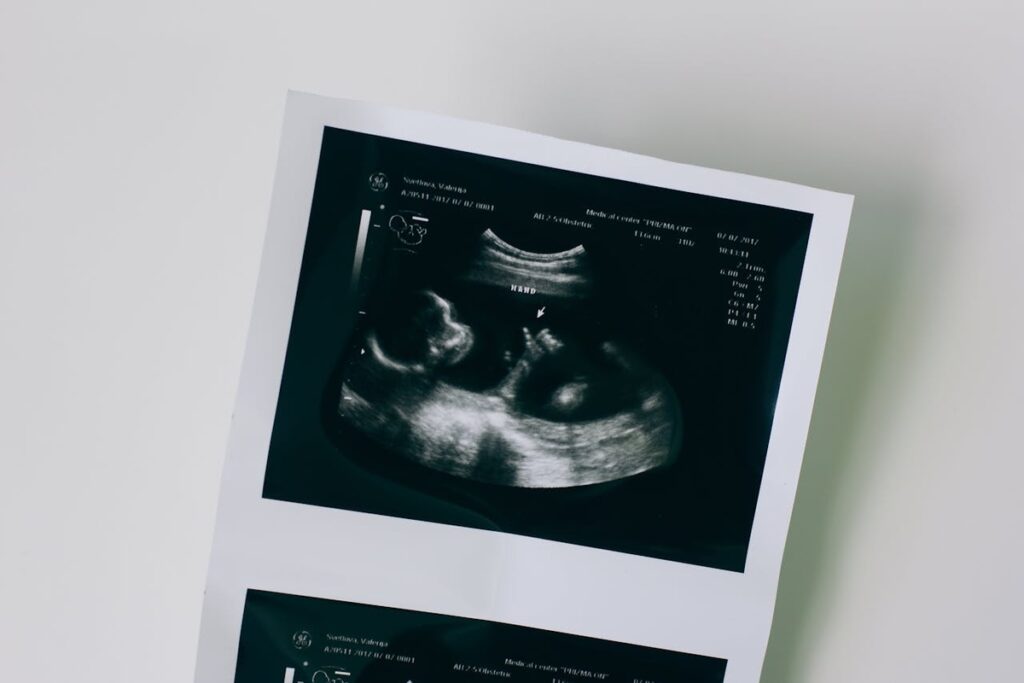

A vasa prévia ocorre quando vasos sanguíneos do bebê passam pelo colo do útero sem proteção, o que os torna vulneráveis à ruptura. “Se houver rompimento das membranas, esses vasos podem se romper rapidamente, resultando em hemorragia fetal grave. Sem diagnóstico prévio, o risco de morte é elevado. Hoje, a conduta padrão é realizar cesariana programada entre 34 e 37 semanas para evitar esse risco — o que pode levar à prematuridade e à necessidade de internação neonatal”, explica Ruano.

No caso apresentado no estudo, a gestante foi tratada na 31ª semana e conseguiu prolongar a gravidez até 36 semanas e 5 dias, quando entrou em trabalho de parto. O bebê nasceu saudável, por cesariana, a pedido da paciente.